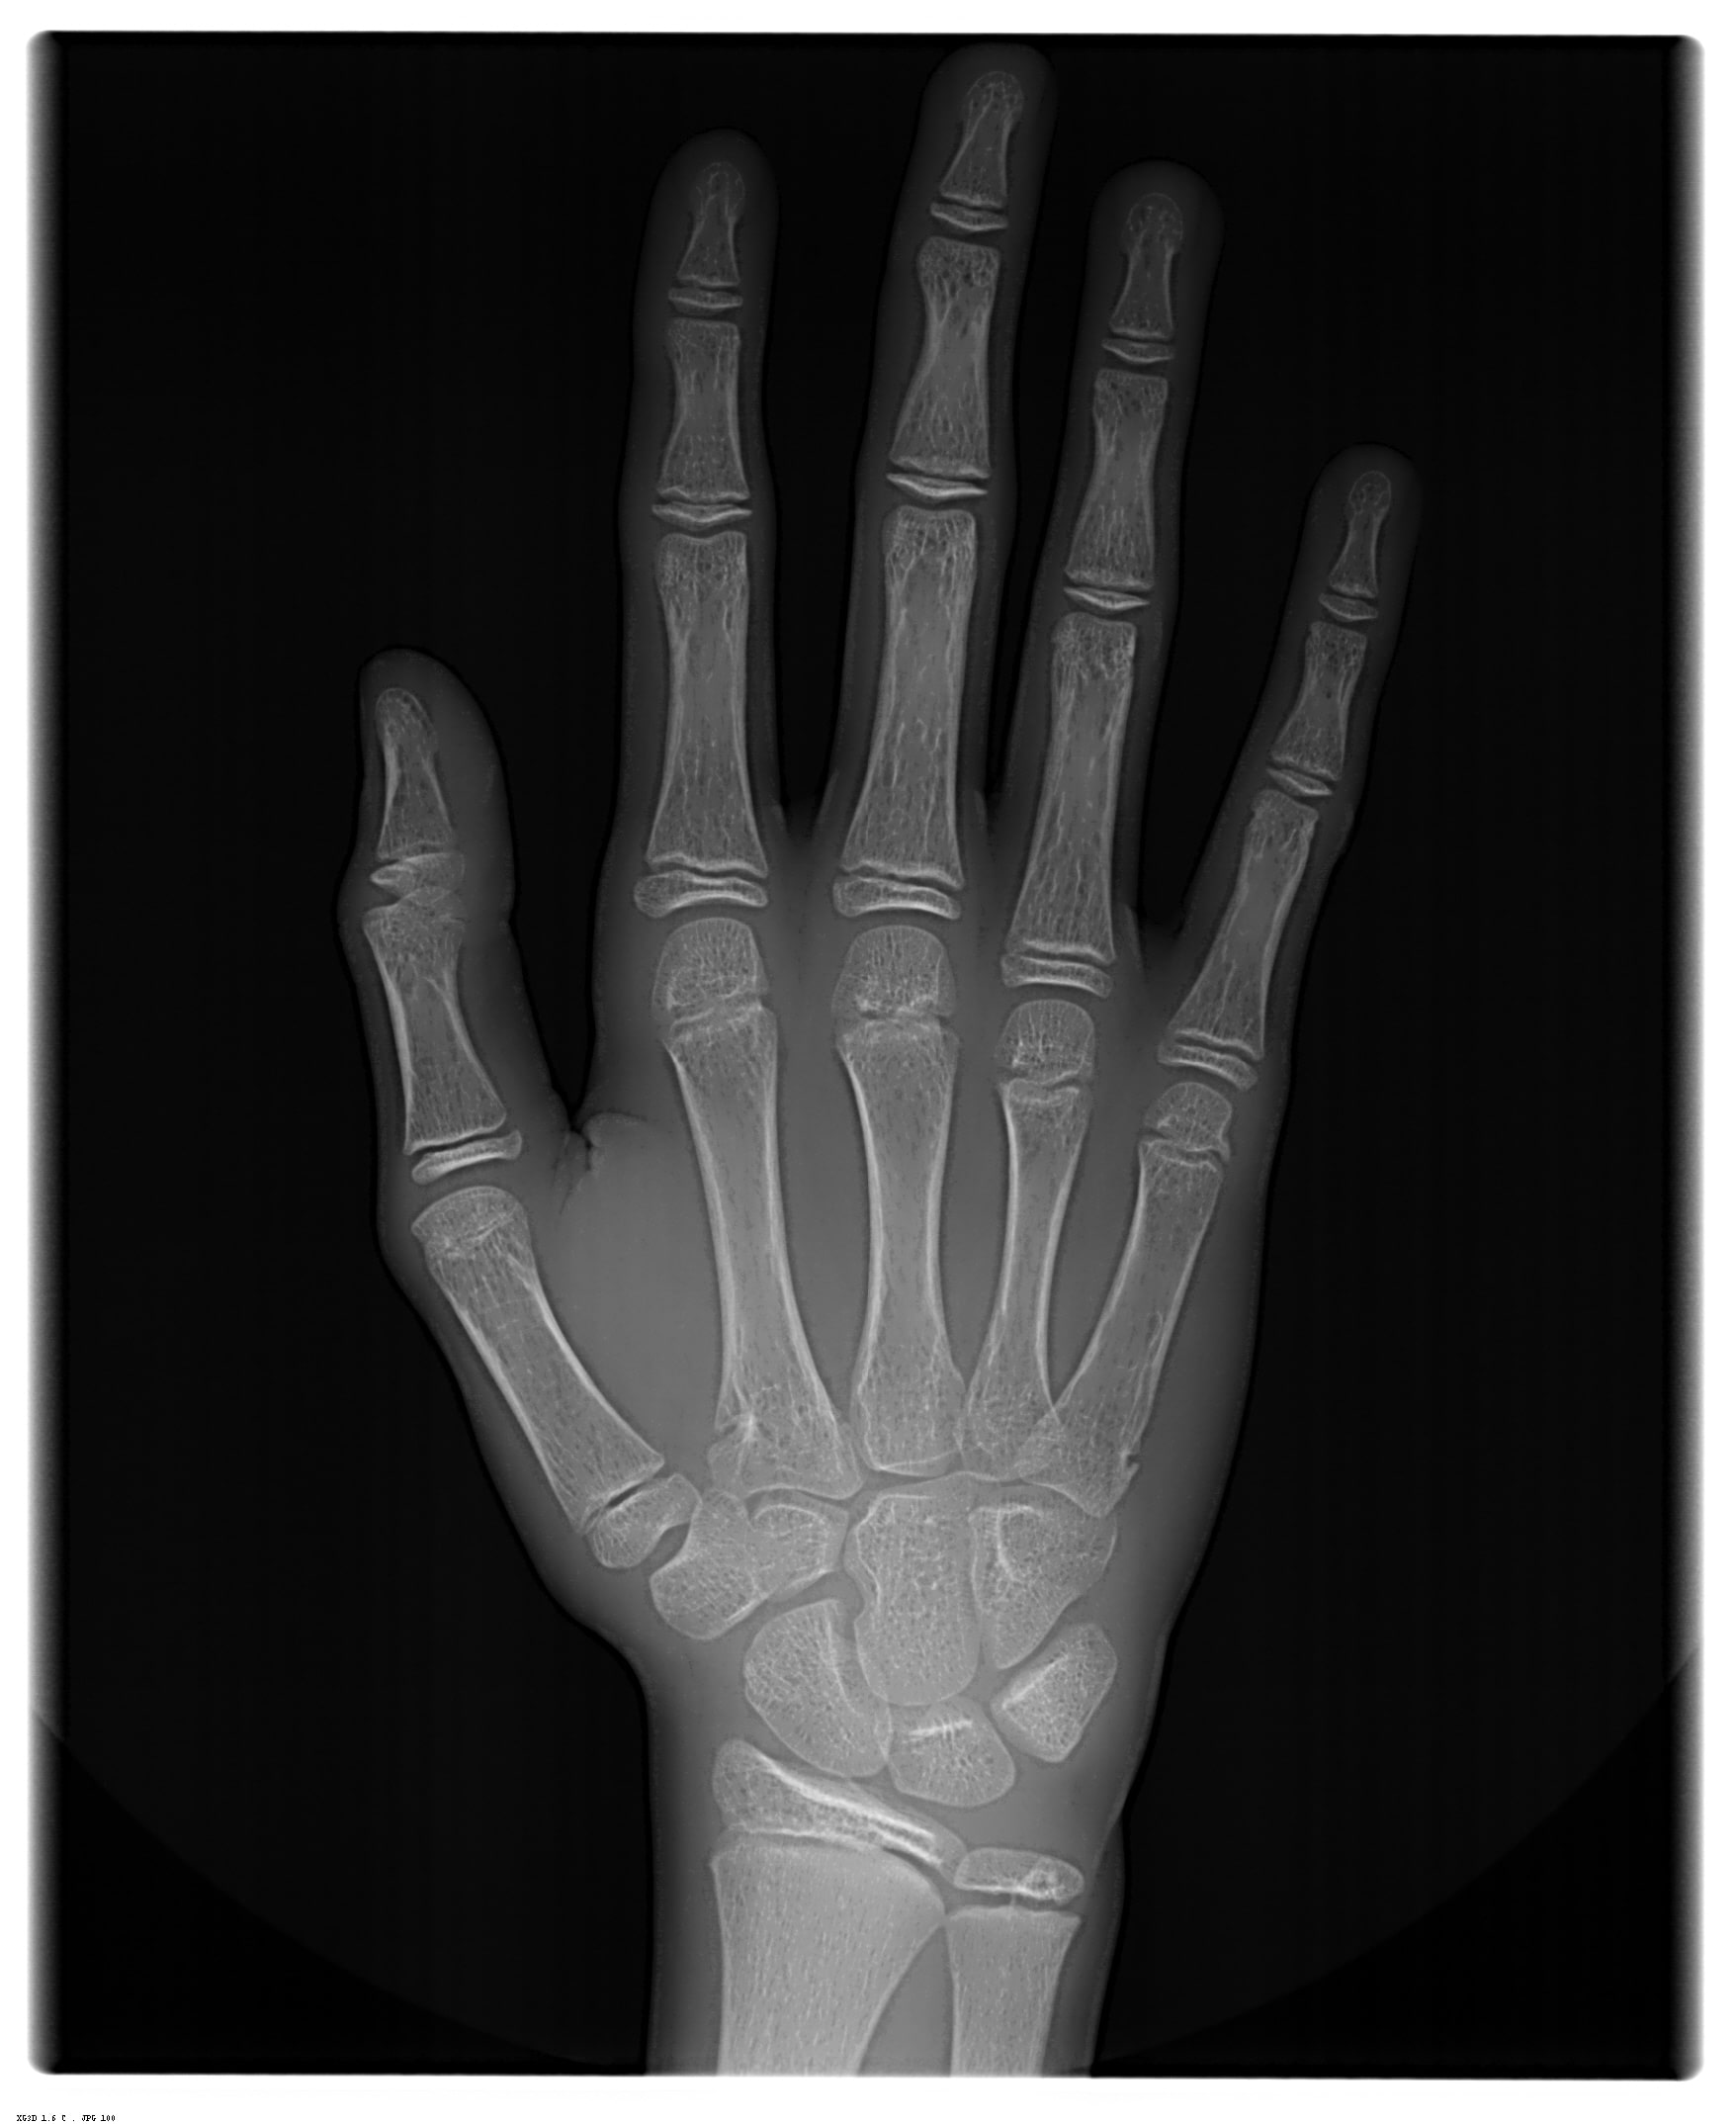

Radiografia de Mão e Punho (Idade Óssea)